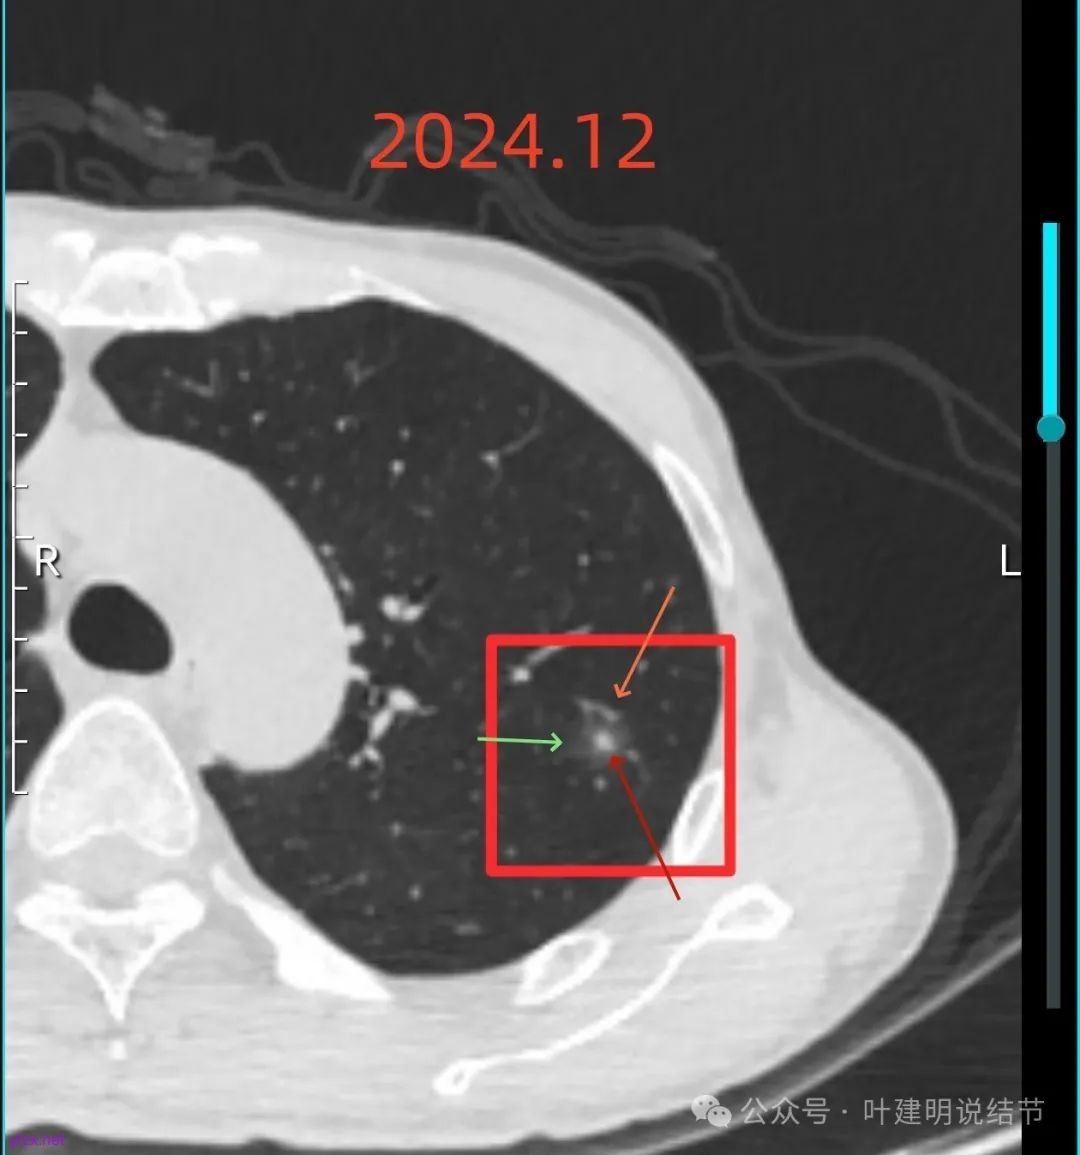

再来看2024年12月时的影像:

右下实性结节两年来没有变化,那它就是良性的可能性大些了,至少目前不考虑干预处理。

右上混合阴影也没有明显进展,则同样要更倾向确实是支气管扩张伴慢性炎与纤维增生的关系,可随访。

左上病灶血管进入了病灶且有异常增粗,边缘有淡的细毛刺的样子。

灶内血管明显,管壁略毛糙,有异常增粗,红色箭头处有点状高密度,边缘有毛刺征。

灶内出现了明显的实性成分,整体轮廓较清。

除了原血管进入外,另外角度也见到其他血管发出分支走向病灶,而且灶内密度不均,实性成分明显。